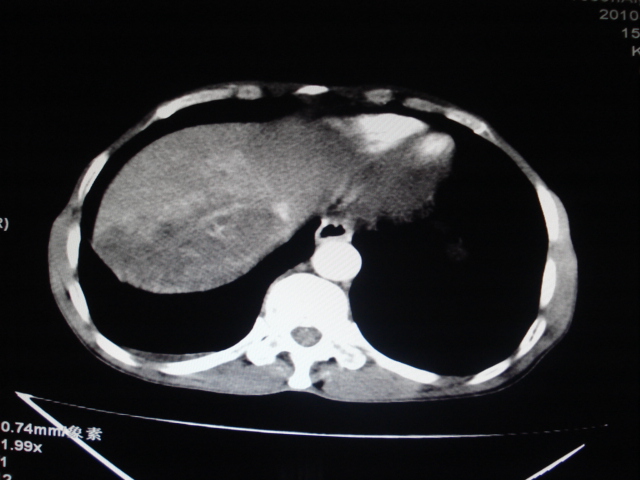

标题: CT24041:肝脏占位,请会诊!

男性,62岁。肝右叶占位,平扫及增强如下,延迟期为15分钟扫描。